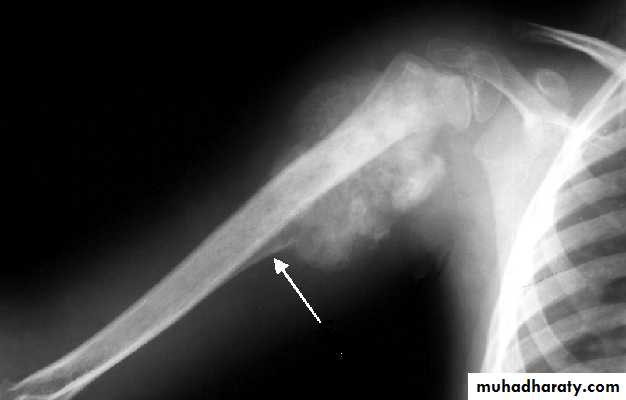

Tumor have slender pedicle directed from growth plate ,,, what it could be ???

Is the direction of pedicle toward joint or away ?????What is being have at upper aspect ???

What is their significance ???

Answer .Osteochondroma Most common benign bone lesion which have their own growth plate)

Pedunculated: slender pedicle directed away from growth plate .The thickness of the cartilage cap above the bony projection is very important

if the thickness > 1 cm of cartilaginous cap by CT, > 2 cm by MRI give high possibility of Malignant transformation

Also Dispersed calcifications in the cap